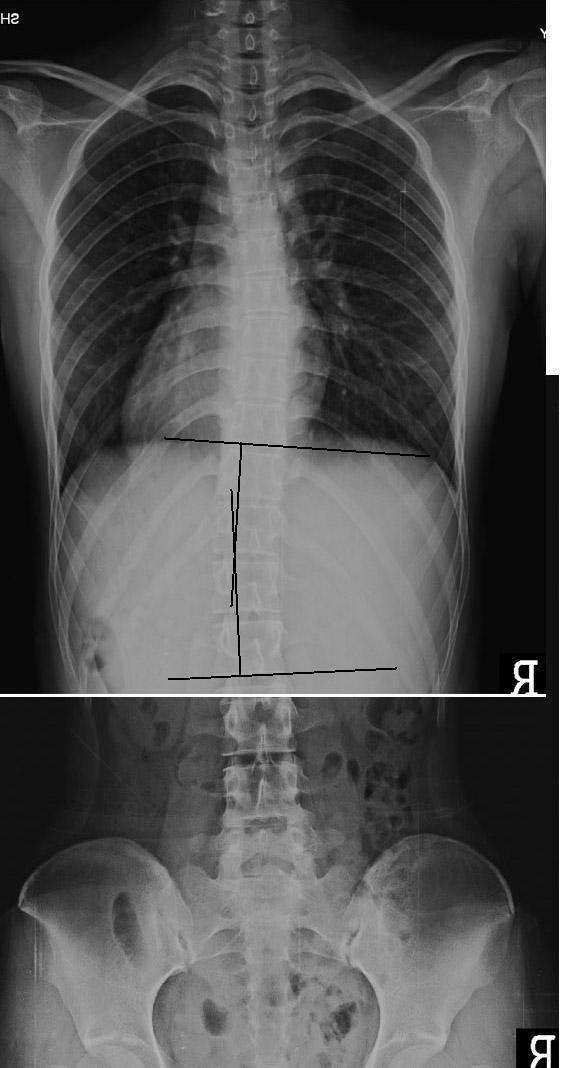

분석 : 척추 측만증 치료 전 21도의 측만에서 치료 후 5도의 측만으로 16도 정도의 호전을 보였습니다.

치료 : 주 1회, 3개월간 치료를 받았습니다. 추나요법을 위주로 치료 하였고 체형 교정 운동인 바태운동을 겸하였습니다.

치료 과정에서의 측만각도 호전을 보였으나 현재 완전한 회복을 이룬 것은 아니므로 지속적인 치료가 필요합니다. 본원에서의 치료를 권해 드리며 추나치료 뿐 아니라 바태체형운동을 겸해서 적극적인 치료를 할 계획입니다. 측만 각도의 개선과 더불어 허리 과전만의 감소가 나타나야 합니다.